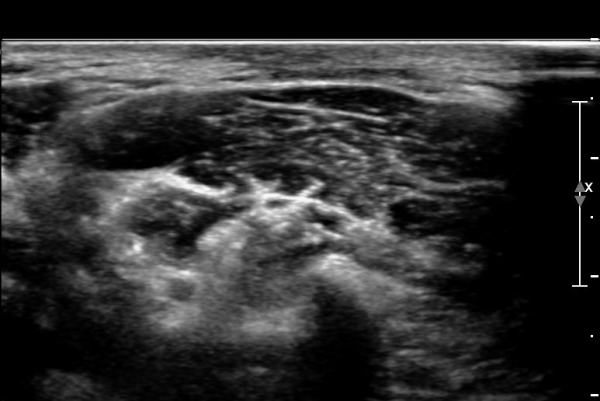

ÃÊÀ½ÆÄ ¼Ò°ß : ¸ñ ¿ÜÃø Á߾ӺΠȾ´Ü¸é°Ë»ç»ó Èä¼âÀ¯µ¹±Ù ÈÄ¹Ý °ß°©°Å±Ù Ç¥Ãþ¿¡¼­ ôÃߺνŰæÀÌ Àú¿¡ÄÚ

¿øÇü ±¸Á¶¹°·Î °üÂûµÈ´Ù(»çÁø 1, 2, 3).